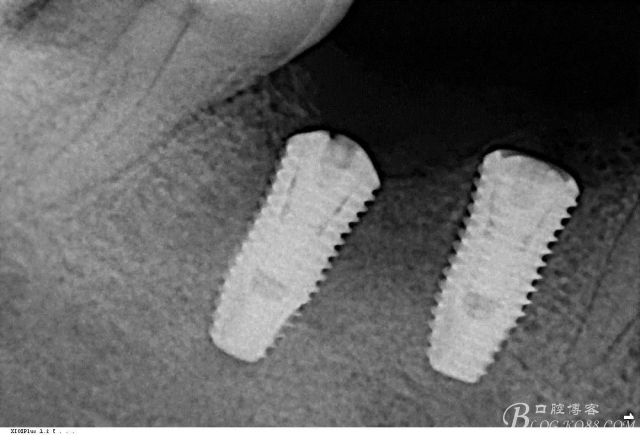

植入植體

C6頰側(cè)填入自體骨,嚴(yán)密縫合關(guān)閉創(chuàng)口

三維檢查種植體位置,方向,平行度